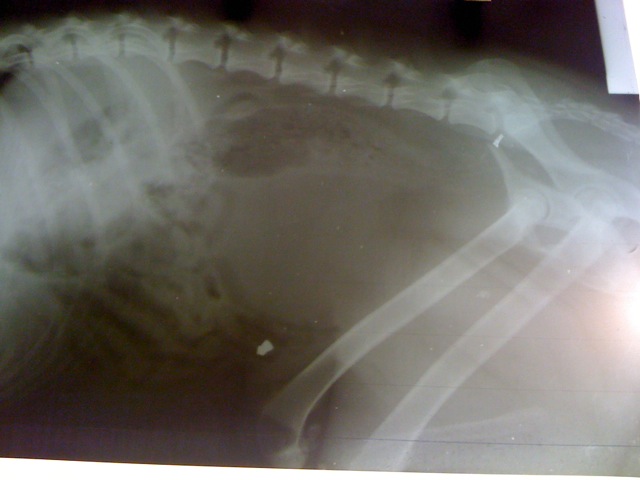

2011.03.08. Képek a kórházból

Ma este elvittük Békéscsabára az Állatkórházba a kutyust, mivel elég komoly és aggasztó tünetei voltak, valamint továbbra sem tudott lábra állni. Nem tudta tartani a vizeletét és a széklete is véres volt. Sajnos a röntgen felvételek medence törést mutatnak, ami magyarázatot ad arra, miért nem tud fölállni. Ami még döbbenetes, hogy a röntgen felvételen egyértelműen látszik egy fegyverből származó golyó és valamilyen fém szilánk a testében, amit valamikor régen szerzett. Ennek ismeretében nem csoda, hogy ilyen nagyon fél az emberektől és megharapta azt, aki segíteni akart neki. Most már jobb lesz minden. Holnap megoperálják, összedrótozzák és lemezelik a széttört csontokat. Délben megyünk érte. Sajnos a gazdája nem jelentkezett. Nagyon jó orvos látja el. remélem, a gyógyulása fájdalom mentesebb lesz, mert már elég sokat szenvedett. És nem csak most.